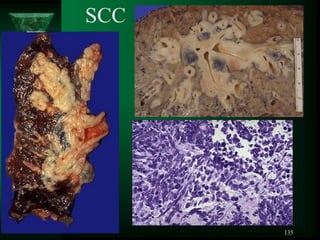

SCC

CARCINOID